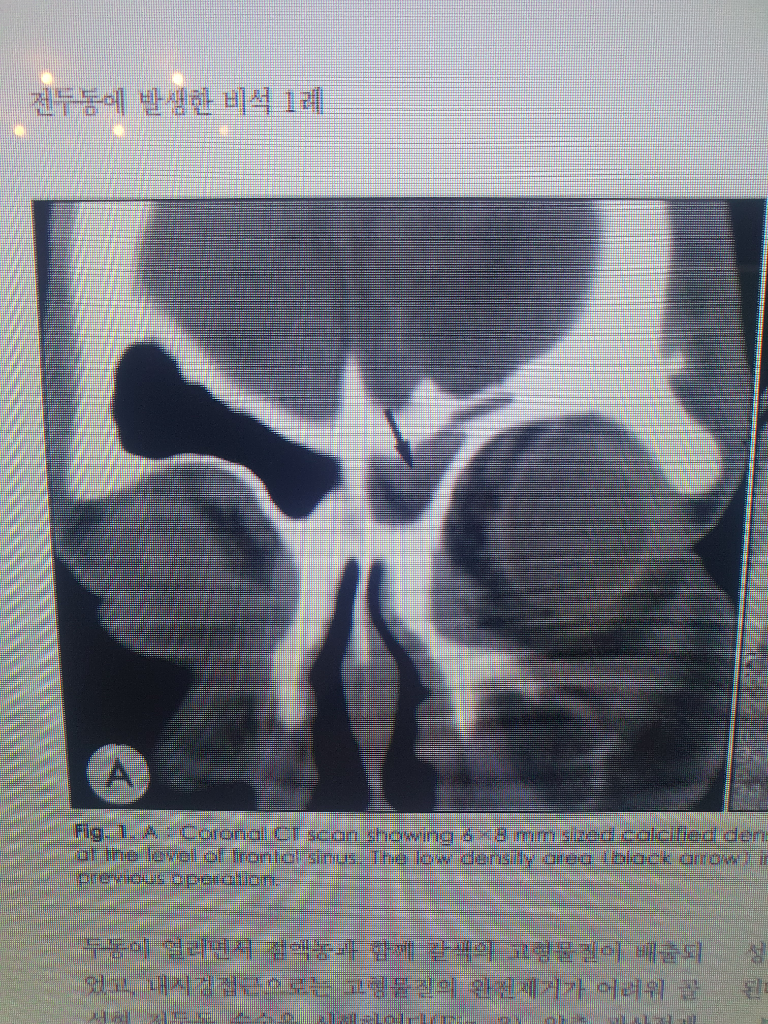

화살표 부분이 6x8mm 석회화 부분이라는데, 석회화라면 보통 하얀색이어야 되지 않나요? 왜 저기서는 회색으로 나왔죠??

(97년 ct사진이라 화질은 그리 좋지 않은것 같아요)

영상 설명을 보면 calcified density라는 말이 나옵니다. 이는 석회화라는 해석보다는 석회를 동반한 음영이라 해석하는 것이 알맞고, 비석 군데군데 석회를 동반했다 정도의 의미를 가진다고 이해하시면 됩니다.